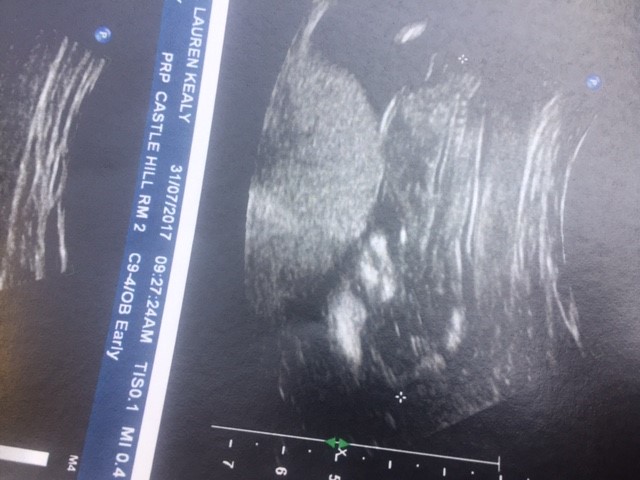

Attachment 37656

Sorry baby was upside down the whole scan! 12 weeks x